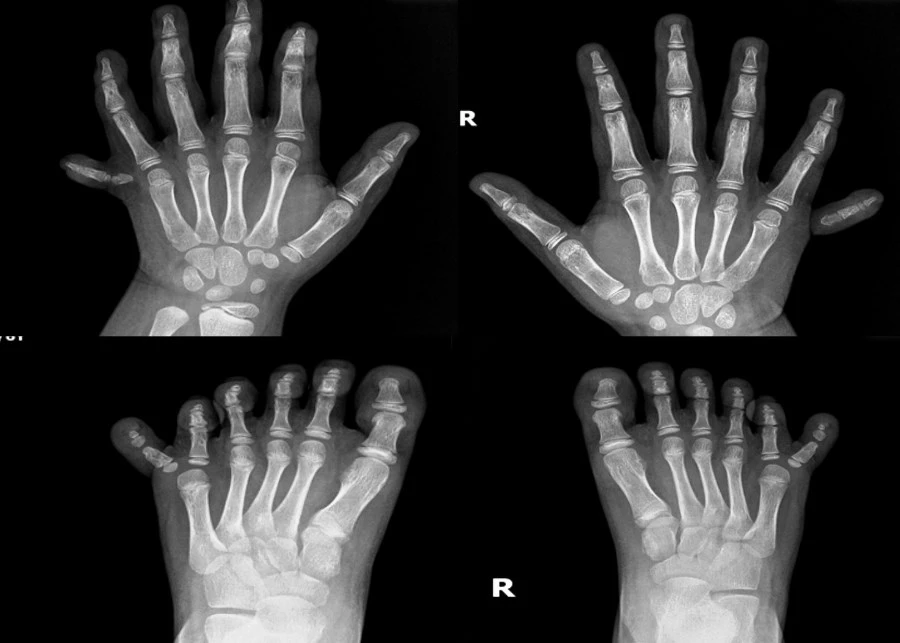

Phim X-Quang về trường hợp 12 ngón tay, 12 ngón chân hiếm gặp. Ảnh: BVCC |

Mỗi bàn tay, bàn chân của bé có đến 6 ngón, tổng cộng bé có 12 ngón tay, 12 ngón chân. Mặc dù các ngón tay chân vẫn phát triển và có xương bình thường nhưng việc dư thừa các ngón khiến cho sinh hoạt của bé bị cản trở, đặc biệt là khi lựa chọn giày, vận động, chạy nhảy.